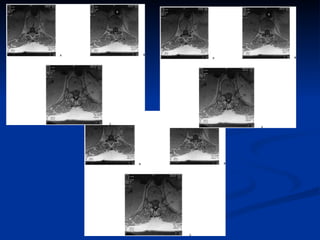

Artéfacts  artefacts de flux :  espace sous arachnoïdien rétromédullaire thoracique, axiales T2 SE rapide    ne doit pas être confondu avec des dilatations vasculaires  artefacts de mouvement:  pulsations cardiaques et aux mouvements respiratoires L’ artefact de Gibbs  (artefact de troncature) hypo-intensité T1 et hyperintensité T2 linéaire centromédullaire parallèle à l’axe de la moelle    ne doit pas être confondu avec une fente syringomyélique. L’ artefact  de déplacement chimique peut effacer le signal de l’un des deux plateaux vertébraux sur les coupes sagittales et frontales pondérées en T1

Artéfacts artefactsde flux : espace sous arachnoïdien rétromédullaire thoracique, axiales T2 SE rapide  ne doit pas être confondu avec des dilatations vasculaires artefacts de mouvement: pulsations cardiaques et aux mouvements respiratoires L’ artefact de Gibbs (artefact de troncature) hypo-intensité T1 et hyperintensité T2 linéaire centromédullaire parallèle à l’axe de la moelle  ne doit pas être confondu avec une fente syringomyélique. L’ artefact de déplacement chimique peut effacer le signal de l’un des deux plateaux vertébraux sur les coupes sagittales et frontales pondérées en T1